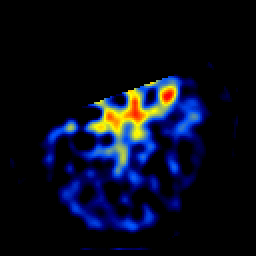

SPECT TL Study #4 -- Slice #12

[Home][Help][Clinical][Tour 1][Tour 2][Tour 3] Slice 12